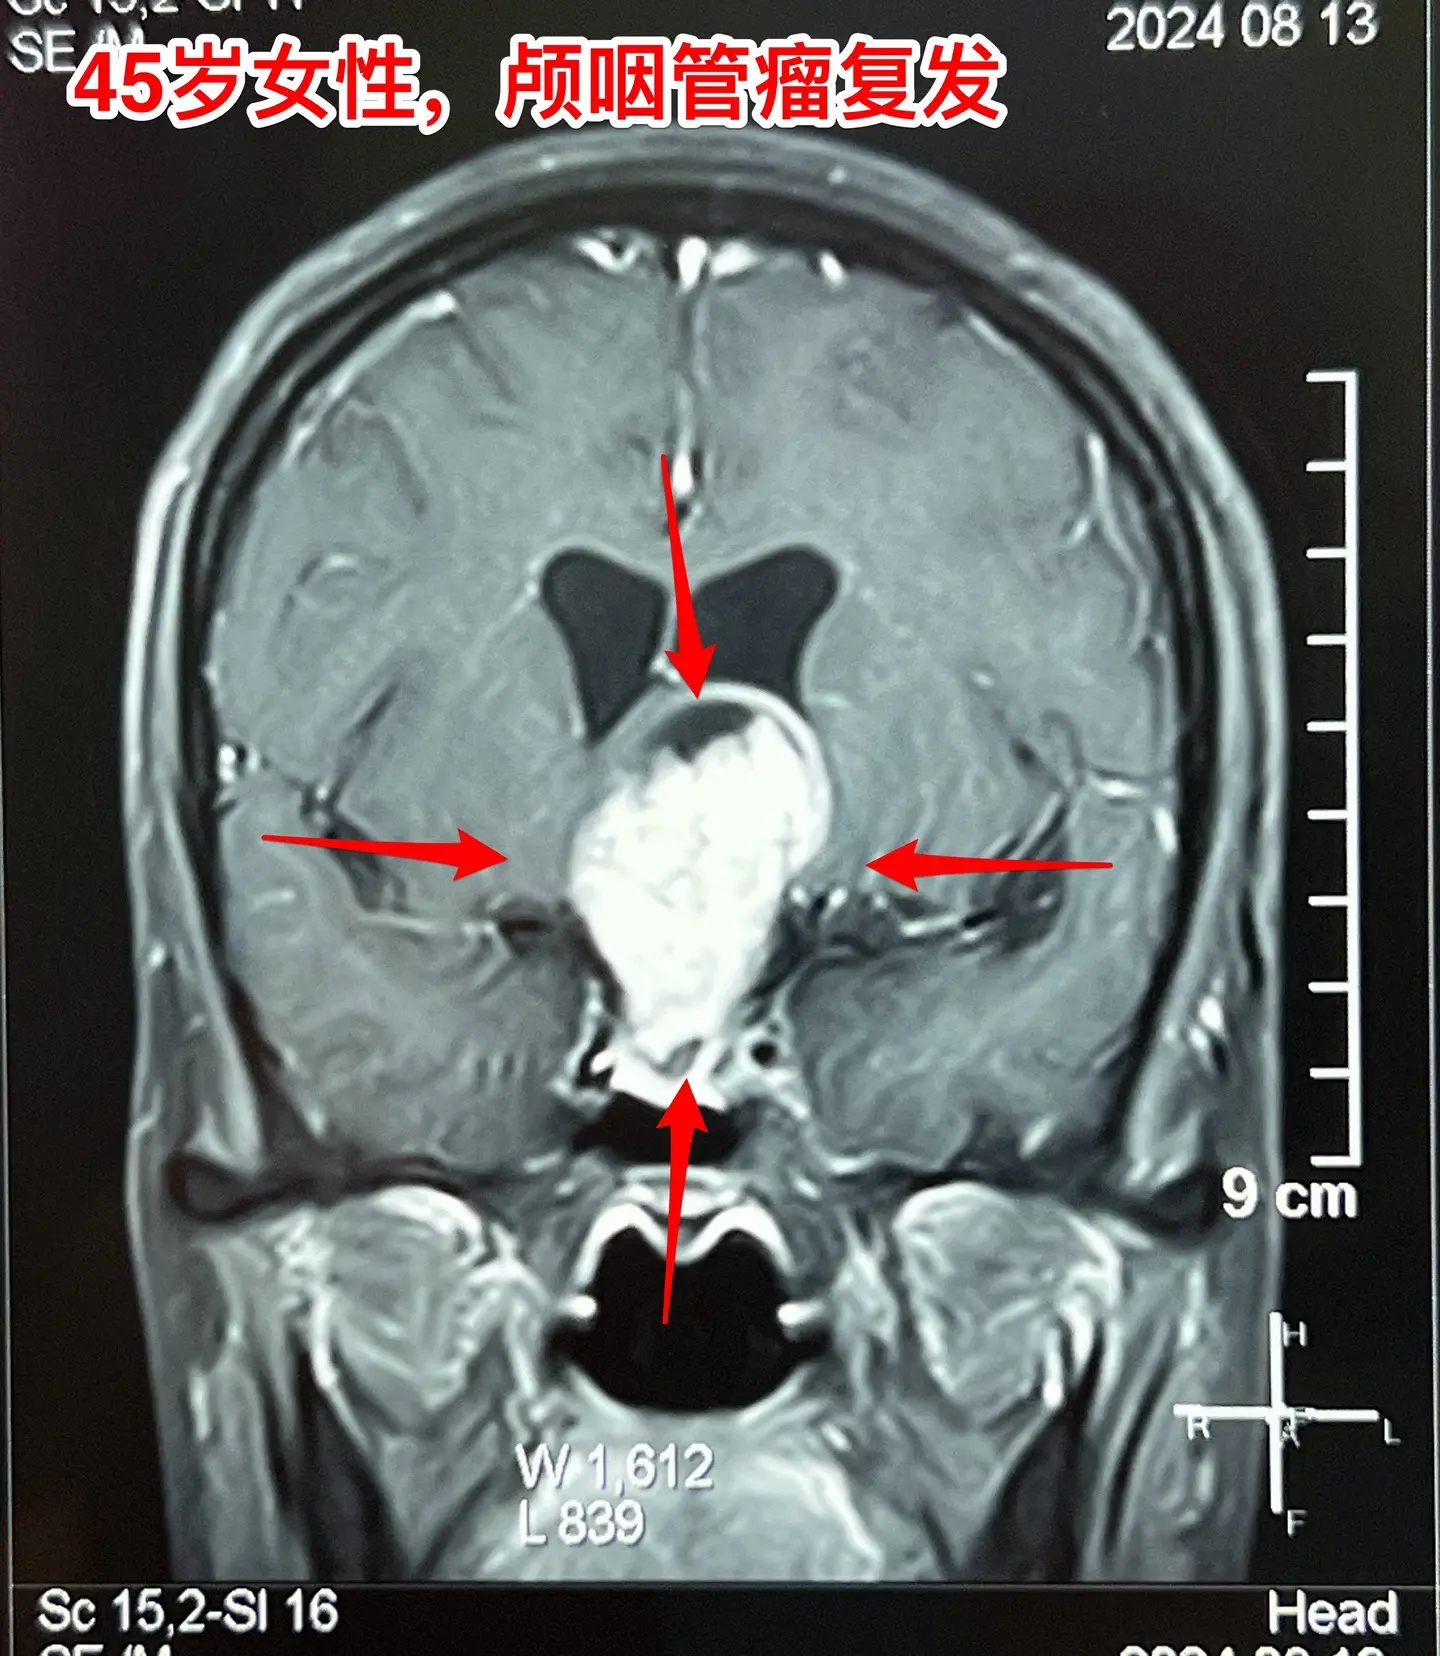

巨大的颅咽管瘤。45岁浙江女性,在外院作了颅咽管瘤手术不到一年,作磁共振显示肿瘤复发,而且体积巨大。 病人视力很差,记忆力也差,精神不好。 这么大的颅咽管瘤一般是需要作手术的。显而易见是这样的手术是很有难度的,很考验医生的技术和能力! 从影像学资料可以看出,这是乳头型颅咽管瘤。如果害怕作手术,对于运气好、经济状况好的病人,也可以试一试靶向药,也许有效。 这个病人选择了作手术!8月16日我们经过九个小时的紧张奋战,将肿瘤完全切除了。手术后CT结果很好。